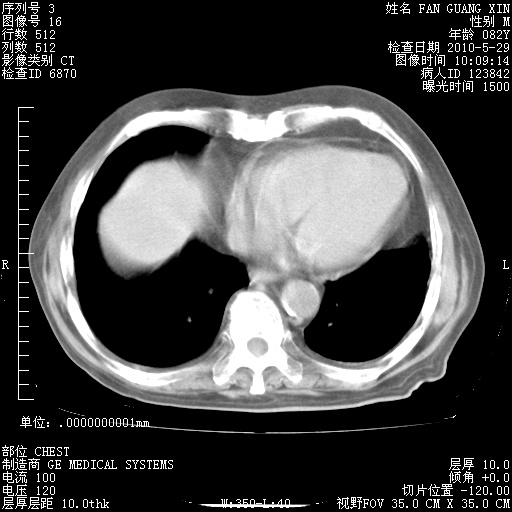

再治疗10天后的肺部CT

再治疗10天后的肺部CT 纵膈窗

阅读此次胸部CT,肺间质渗出性改变较入院时有吸收。目前从体温、白细胞、中性分叶明显增高,肯定存在细菌感染(发生医院感染哦,若无消化道及泌尿系统等感染的依据,肺部感染可能大)。若你院头孢哌酮舒巴坦钠耐药率较高,同意你的方案,若48小时体温仍高,可考虑使用碳青霉稀类抗菌药物,同时可予超声雾化、注意滴数时加大液体量。白蛋白33.30g/L较低哦,需加强营养等支持治疗。